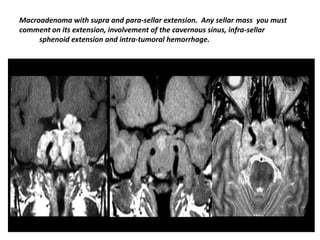

Macroadenoma with supra and para-sellar extension. Any sellar mass you must

comment on its extension, involvement of the cavernous sinus, infra-sellar

sphenoid extension and intra-tumoral hemorrhage.